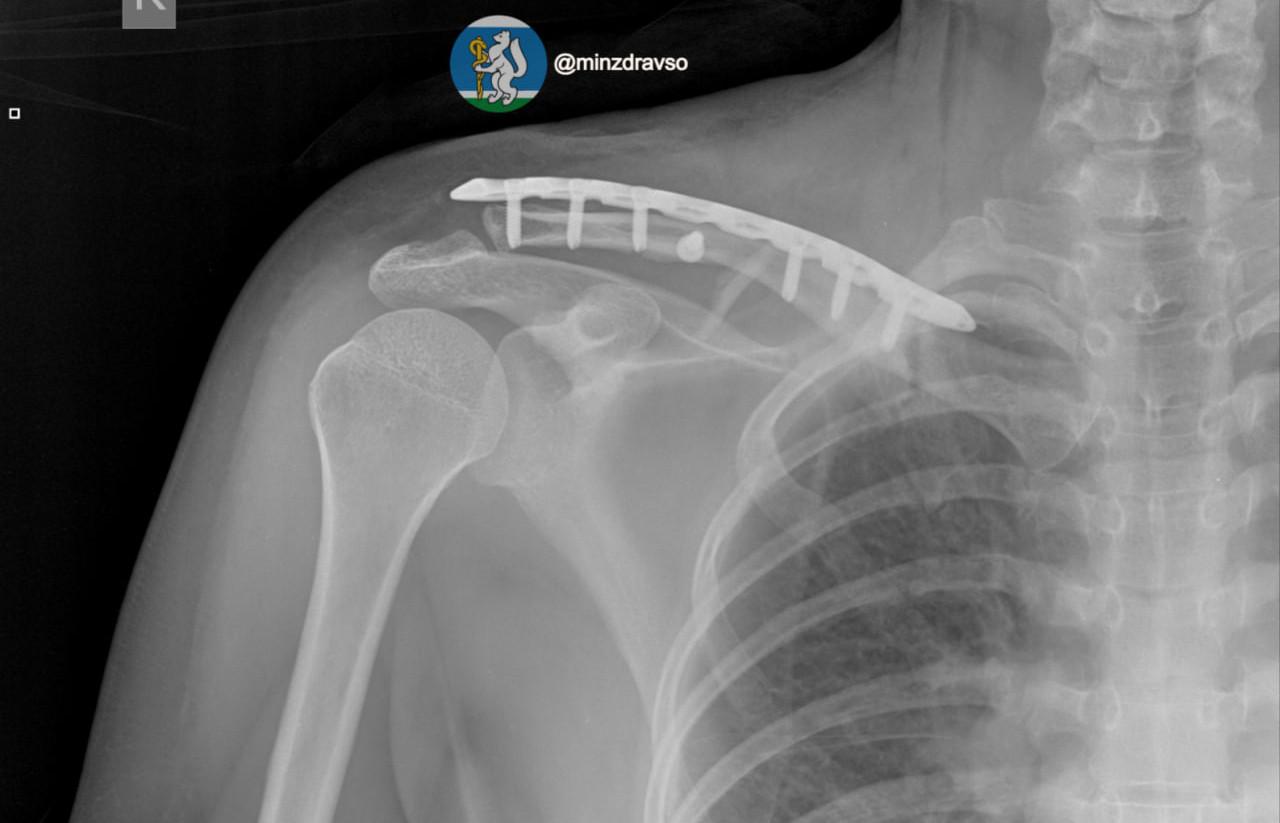

По данным министерства здравоохранения Свердловской области, благодаря вовремя прибывшей бригаде «скорой» удалось сохранить драгоценные минуты и доставить женщину в больницу, где в течение первых 15 минут были проведены все необходимые исследования. Врачи диагностировали тяжелую политравму, включающую закрытую черепно-мозговую травму, ушиб головного мозга, повреждение челюстно-лицевых костей, ребер, двусторонний пневмоторакс, оскольчатый перелом правой ключицы и раздробленные кости таза.

«Крайне тяжелое повреждение таза представляло высокий риск массивной кровопотери, поэтому борьба за жизнь пациентки началась с немедленной стабилизации ее состояния. Медики качественно скрепили отломки костей всех поврежденных сегментов костей и таза аппаратами внешней фиксации.   Профессионализм и опыт врачей, их высочайшая квалификация и плановое совершенствование экстренной медицинской помощи в Свердловской области подарили пациентке получить второй день рождения», — отметили в минздраве региона.

Аппараты внешней фиксации помогли пациентке минимизировали последствия травм, тем самым сохранив качество жизни. Сейчас женщина уже дома с семьей.